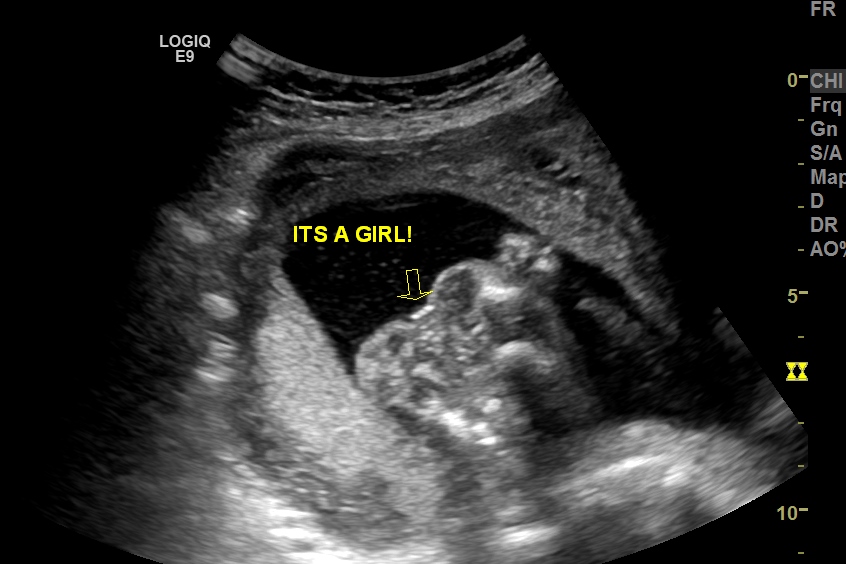

We are still in shock don't think I will believe it till I hold her. Please give me your honest opinions what do you think? After 3 boys I am so excited yet need some reasurance. Thank you for your time.

Attachment 31101